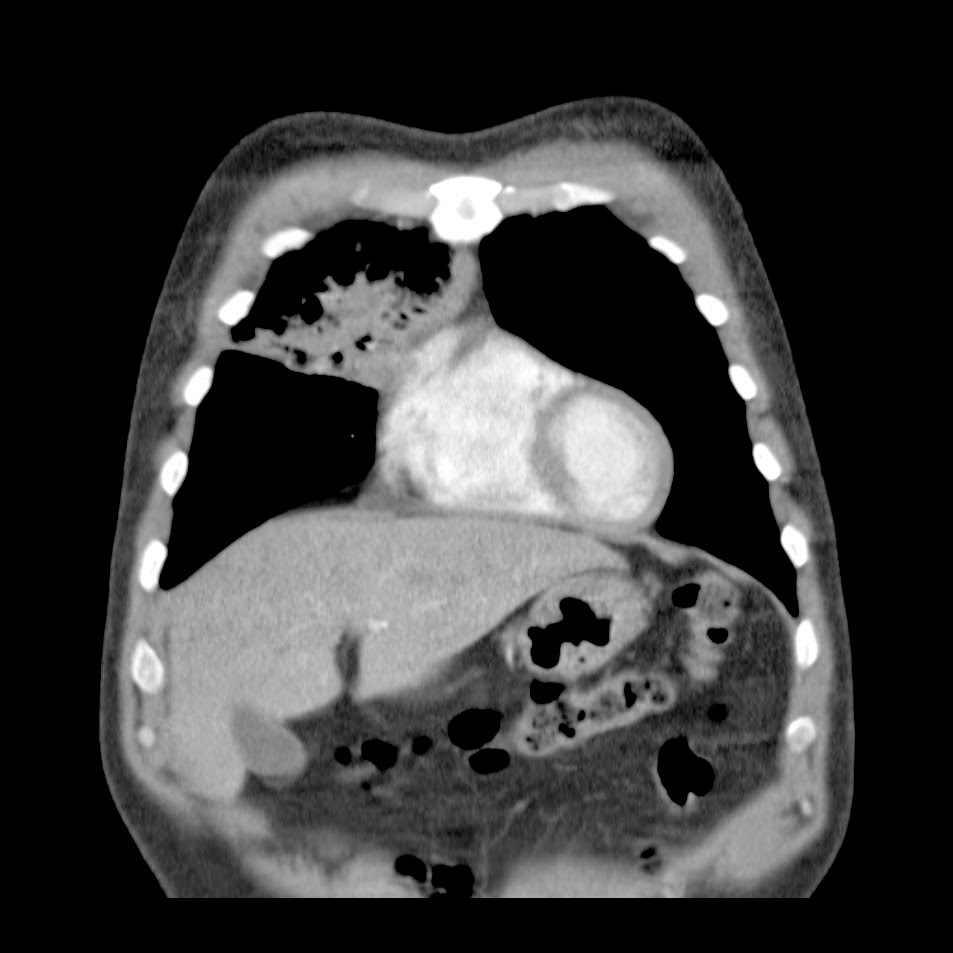

Caso interesante #6

Otro casito de un tórax para localizar la consolidación

Caso interesante #5

Paciente con dolor en hipocondrio derecho.